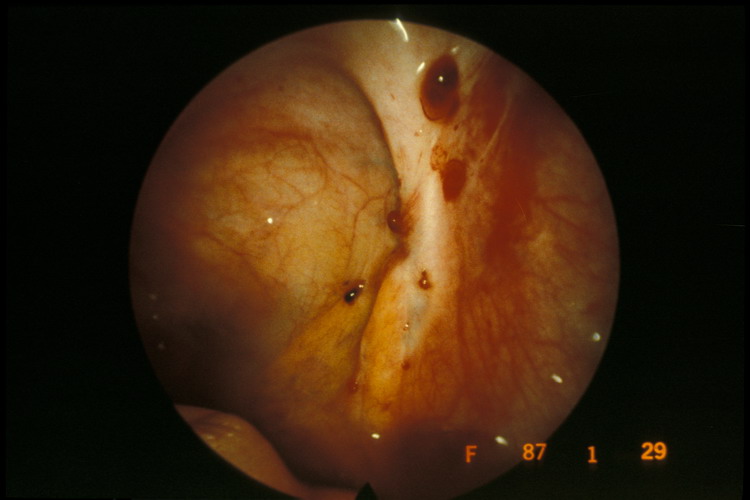

La tecnica diagnostica standard è la laparoscopia; che consiste però in un intervento chirurgico con potenziali complicazioni, rare ma gravi. I metodi diagnostici per immagini sono attendibili per le donne che soffrono di endometriosi moderata o grave, ma per quelle che hanno un’endometriosi minima o lieve è necessario trovare una procedura non invasiva o minimamente invasiva.

Studi precedenti, condotti da ricercatori in Australia e Giordania hanno dimostrato che c’è una densità molto maggiore di fibre nervose nell’endometrio (rivestimento uterino) delle donne affette da endometriosi rispetto alle donne che non hanno tale malattia. Gli stessi ricercatori infatti hanno scoperto che questa densità di nervi non è associata a nessun’altra malattia. Queste scoperte preliminari hanno ispirato una nuova ricerca di strumenti diagnostici non invasivi o minimamente invasivi.